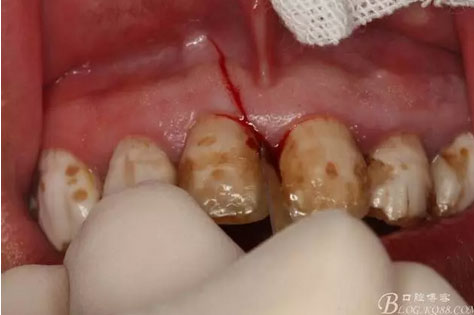

圖7.11近中的垂直切口

圖8.垂直切口+齦溝內(nèi)水平切口,水平切口延至23遠(yuǎn)中乳頭。